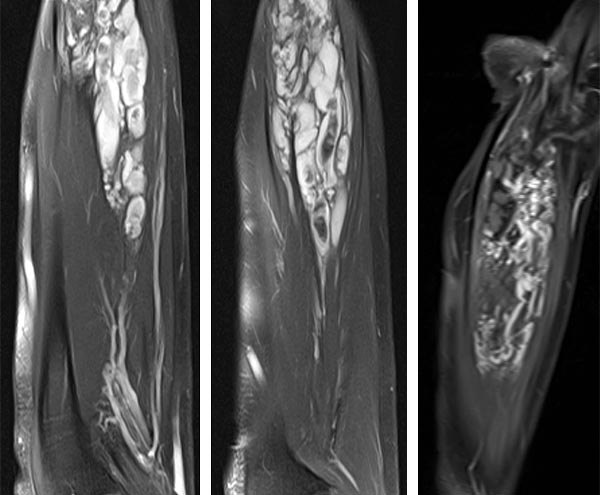

MRI of the forearm in T2-weighted images with spectral fat saturation (left, middle). The characteristically hyperintense, dilated venous convolutes are shown. These lesions enhance contrast medium in the late phase (T1 after contrast; right). The central thromboses appear within these caverns as hypointense areas.